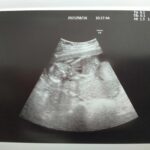

妊婦健診*16w4d

2021/8/16